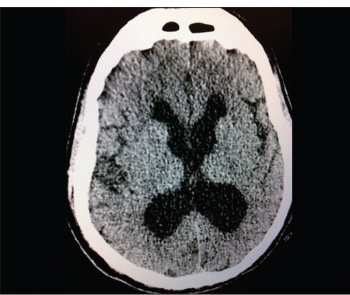

He went to his bed normally the night before with no prior history of acute illnesses apart from his usual flares of rheumatic joint pains which are controlled with oral and parenteral non-steroidal anti-inflammatory drugs (NSAIDs) by his GP, although later a friend of the patient stated that he was texting him misspelled messages for the past two days, however, he wasn’t particularly confused or showing any behavioural change. His BP was 208/143 at scene by the ambulance crew. In the ED he was febrile and comatose (GCS 6/15) with no spontaneous limb movements. The initial CT brain was reported as communicating hydrocephalus which was likely old with no other findings (see Figure 1).

Figure 1. The initial CT brain at presentation showing the communicating hydrocephalus(click to enlarge)